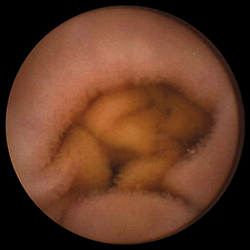

де еще «Push-and-Pull-Enteroskopie» (PPE). Уже из названия становится понятным и сам принцип этого предложенного в 2001 г. японцами (Yamamoto H. et al., 2001) и впервые в 2003 г. примененного на Западе исследования. Передвижение по тонкому кишечнику телескопически выдвигаемого зонда длиной около двух метров, состоящего из непосредственно энтероскопа и наружного зонда большего диаметра, осуществляется путем «нанизывания» на эндоскоп кишки, что становится возможным за счет периодического раздувания и перемещения относительно друг друга двух баллонов, один из которых находится непосредственно на конце эндоскопа, а другой — на конце наружного зонда. Так как по структуре своей двухбаллонный энтероскоп является обычным эндоскопом, он обладает и всеми его

преимуществами — возможностью промывать оптику во время исследования (что особенно ценно при диагностике кровотечений), проводить биопсии и, самое главное, осуществлять эндоскопические вмешательства. Именно поэтому зачастую капсульная эндоскопия (естественно, при положительном результате) дополняется двухбаллонной энтероскопией. Введение энтероскопа, как правило, осуществляется перорально ортоградно, только в редких случаях (например, при недостаточной инспекции кишечника или выявленной во время капсульной эндоскопии локализации источника кровотечения в дистальных отделах тонкого кишечника) необходимо дополнительное проведение ретроградной трансанальной энтероскопии. Длительность исследования составляет в среднем два часа, естественно, без внутривенного наркоза (как правило, хватает обычной седоанальгезии) тут не обойтись.

Первые результаты клинических исследований эффективности РРЕ выглядят весьма обнадеживающе — около 80% энтероскопий являются результативными. При этом в каждом втором случае было успешно проведено эндоскопическое лечение (лазерная коагуляция, дилатация стенозов или полип-

эктомия), а у каждого четвертого пациента это ис-

следование сыграло решающую роль в выборе дальнейшей медикаментозной тактики (как, например, при болезни Крона) или показаний к радикальному хирургическому лечению (при ее осложнениях).